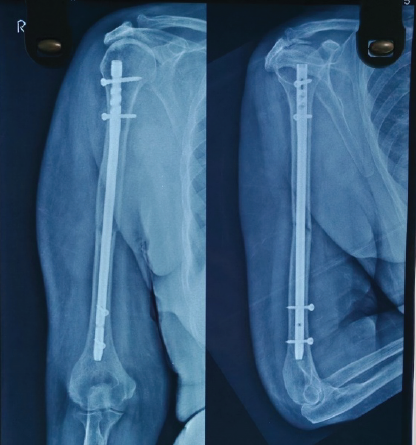

Reduction was confirmed fluoroscopically. Soft-tissue dissection was kept to the minimum required. The wound was thoroughly irrigated, hemostasis achieved, and the rotator cuff repaired carefully. The deltoid interval was closed, and sterile dressings were applied. Post-operative X-ray showed stable fixation (Fig. 4).

Figure 4: Immediate Post-operative X-ray showing nail in situ.

The patient was supported in a sling, and from the 1st post-operative day, she began elbow, wrist, and hand exercises. Passive shoulder mobilization was initiated on day 2. Regular dressing was done. Staples were removed on POD-14. Patient’s range of motion (ROM) improved progressively and attained nearly full ROM by 6th week postoperatively, and X-ray showed good bony union (Fig. 5).

Figure 5: One month old post-operative X-ray showing good bone union.